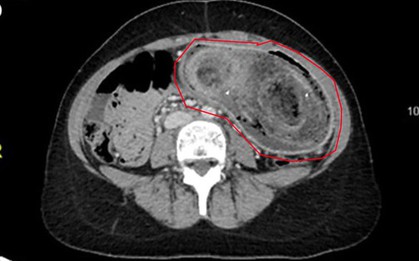

Một trường hợp y khoa gây sốc vừa được ghi nhận tại Tanzania: một người đàn ông 44 tuổi đến bệnh viện vì vùng ngực dưới núm vú phải chảy dịch mủ kéo dài 10 ngày. Bệnh nhân không hề sốt, không khó thở, cũng không có biểu hiện đau đớn nào bất thường.